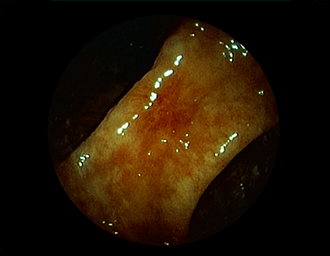

②胃潰瘍(Stage H1)・治療後18日目

胃角部小弯の潰瘍。潰瘍辺縁は平滑で、白苔は部分的に薄い箇所もあり、全周性に再生上皮を認める。